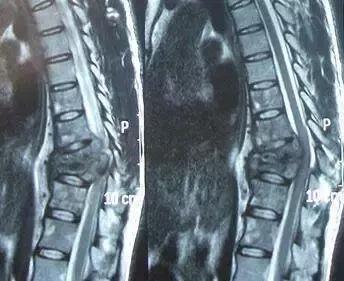

3.MRI 诊断可清晰的显示椎体、椎管、椎间盘及椎旁肌肉受累情况以及椎体周围脓肿形成情况。MRI 在脊柱结核诊断准确性、发病程度和早期诊断方面发挥着重要作用。